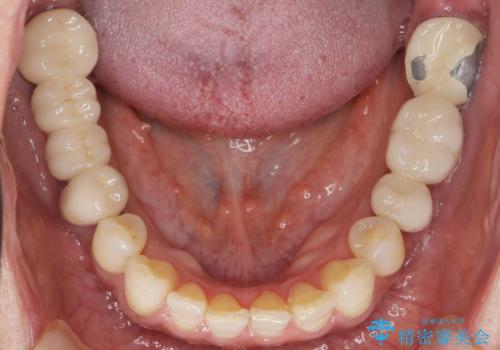

- 奥歯の痛みを主訴に来院された患者様です。

精査したところ、ブリッジの支台歯となっている左下の奥歯(左下7)は大きなう蝕により神経が死んでいました。

根管治療後、メタルボンドブリッジによる補綴治療を行いました。